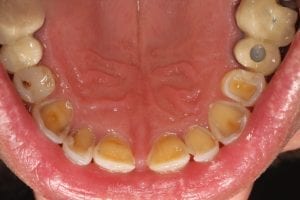

Professeur Dr Olze : Les premières alertes sont subtiles : les dents raccourcissent peu à peu. Les incisives, en particulier, perdent de leur superbe et cela se remarque soudain à l’avant de la bouche.

Quand l’émail disparaît totalement, la dentine, plus foncée, fait surface. À ce stade, il n’est pas rare que les sensibilités dentaires s’installent.

Des troubles de la prononciation peuvent aussi apparaître. Mais ce n’est pas tout : la modification de la hauteur de la morsure peut entraîner des pressions inhabituelles entre les dents du haut et celles du bas, provoquant un déplacement des dents à l’avant de la mâchoire supérieure. Progressivement, des troubles de l’articulation temporo-mandibulaire se développent. Certains patients décrivent alors des tensions, des douleurs musculaires, parfois des gênes dans la gorge.